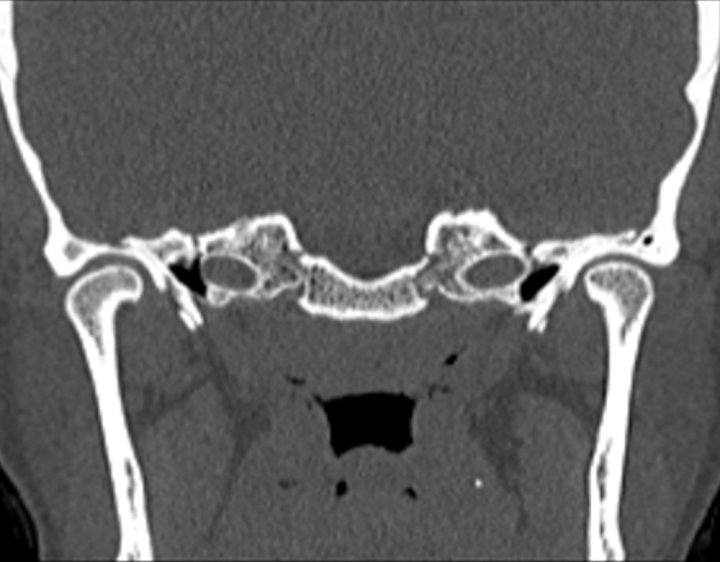

Click any image for labels.